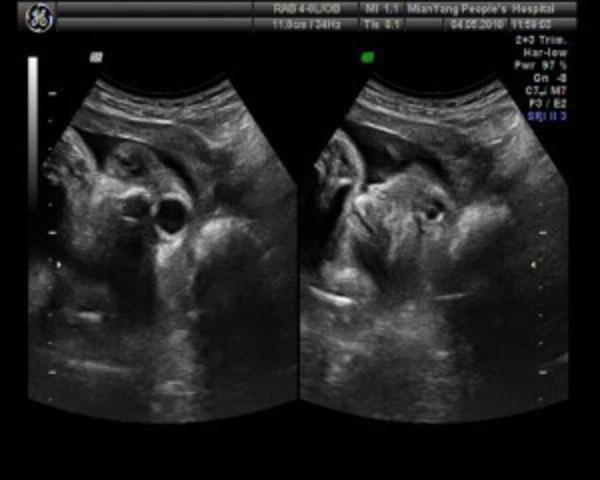

(6)孕八周:胎儿长约1.66cm,胎形已定,可分出胎头、体及四肢。B超可见胎囊约占宫腔一半,可见卵黄囊。胎宝宝的心脏开始跳动了。

(7)孕九周:9周的胎儿已经长到2.15cm了,胎儿头大于胎体,各部表现更清晰,头颅开始钙化、胎盘开始发育。B超可见胎儿轮廓更清晰。

(8)孕十周:此时胎儿长到2.83cm了,胎儿各器官均已形成,胎盘雏形形成。B超可见胎囊开始消失,月芽形胎盘可见,胎儿活跃在羊水中。

(9)孕十一周:胎儿长到3.62cm,胎儿各器官进一步发育,胎盘发育。B超可见胎囊完全消失,胎盘清晰可见。

(10)孕十二周:胎儿长到4.58cm,外生殖器初步发育,可测双顶径,可诊断是否畸形,此后各脏器趋向完善,胎儿眼睛已经形成了。